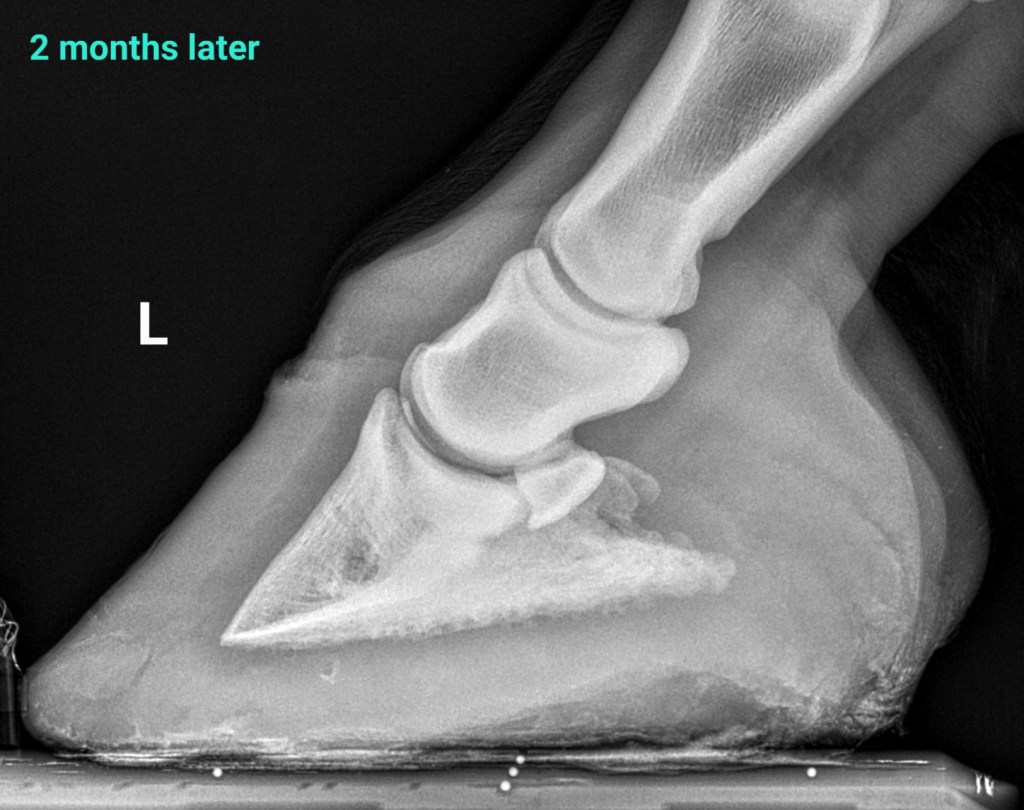

2 months later the horse is sound, he has doubled his sole depth, and improved alignment. I gradually reduced the size of heel elevation and finally removed the Ultimates.